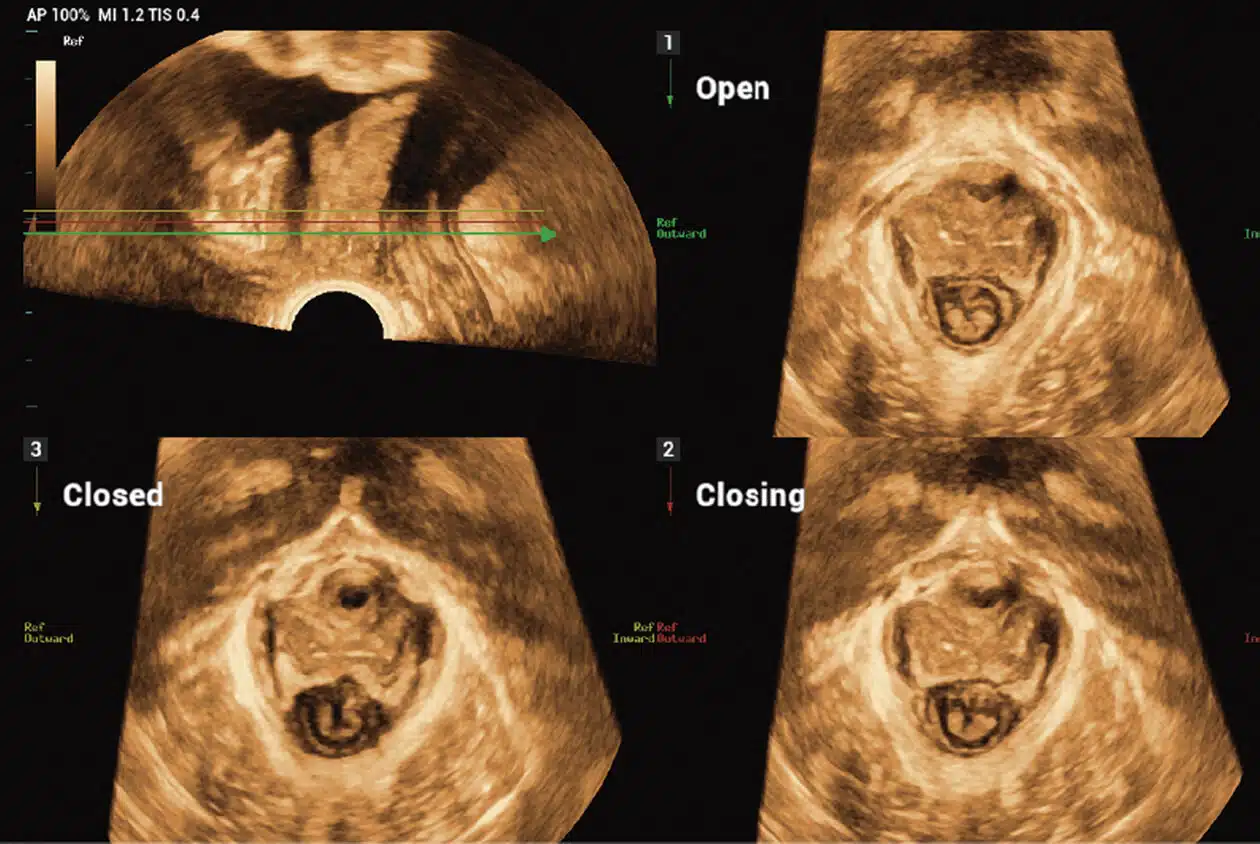

• Smart-Pelvic_Imagyn-I9.jpg-1

Smart Pelvic

Pelvic Floor Measurements

Enables users to quickly obtain 2D/3D automated GYN measurements of the pelvic floor by setting up a baseline and tracing the border of Levator Hiatus automatically.